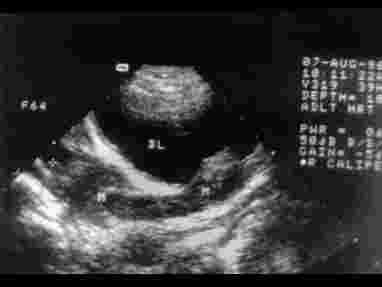

第123例附图5 左输尿管癌血流显示,外院B超误诊为膀胱癌

第123例附图6 右输尿管癌

第123例附图7 右输尿管癌